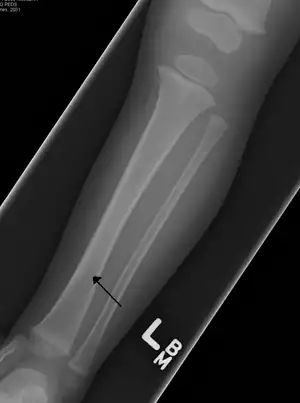

Toddler's fracture

Toddler's fractures are bone fractures of the distal (lower) part of the shin bone (tibia) in toddlers (aged 9 months-3 years) and other young children (less than 8 years).[1] The fracture is found in the distal two thirds of the tibia in 95% of cases,[1] is undisplaced and has a spiral pattern. It occurs after low-energy trauma, sometimes with a rotational component.

Typical symptoms include pain, refusing to walk or bear weight and limping -bruising and deformity are absent. On clinical examination, there can be warmth and swelling over the fracture area, as well as pain on bending the foot upwards (dorsiflexion). The initial radiographical images may be inconspicuous (a faint oblique line) and often even completely normal.[3] After 1–2 weeks however, callus formation develops. The condition can be mistaken for osteomyelitis, transient synovitis or even child abuse. Contrary to CAST fractures, non-accidental injury typically affect the upper two-thirds or midshaft of the tibia.